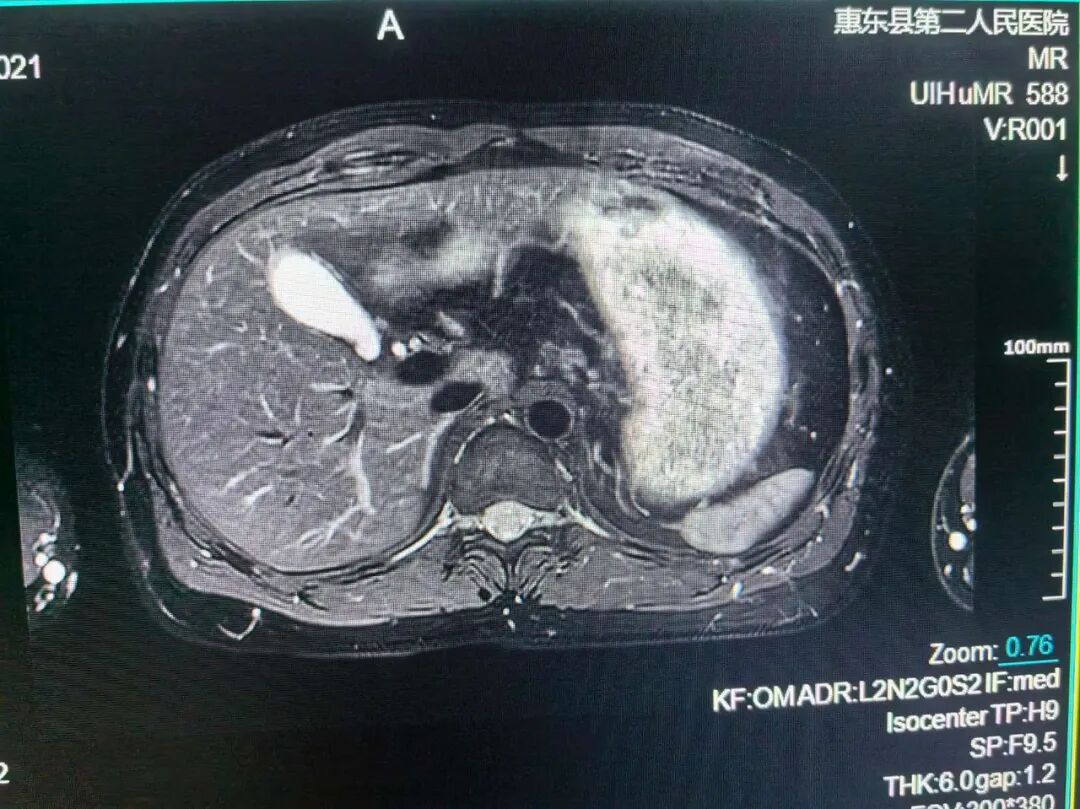

肝胆脾胰MRI检查

肝脏、胆系、胰腺、脾脏的原发性或转移性肿瘤,以及肝海绵状血管瘤;肝寄生虫病:如肝包虫病;弥漫性肝病:如肝硬变、脂肪肝、色素沉着症;肝、胆、胰、脾先天性发育异常;胆道梗阻:明确梗阻的部位与性质;肝脓肿;⑦肝局限性结节增生和肝炎性假瘤;⑧手术、放疗、化疗及其它治疗效果的随访和观察;⑨胰腺炎及其并发症。